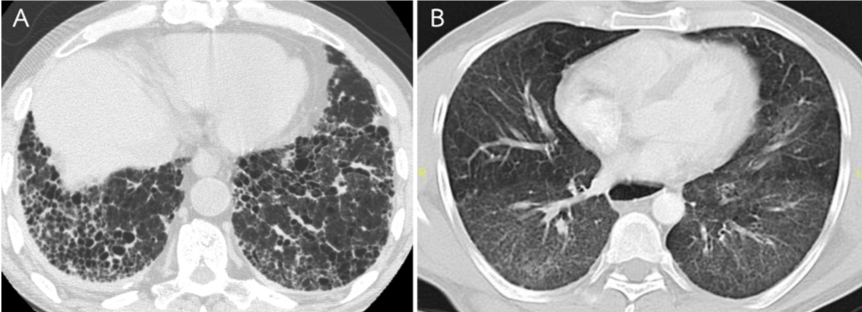

Chest X-ray is helpful but has limited sensitivity and specificity in the diagnosis of ILD. HRCT is more sensitive in the detection and characterization of ILD. The most common HRCT findings include consolidation, reticulation, ground-glass opacities, and peri-bronchovascular thickening as shown in Figure 1B and Table 5 [1]. Honeycombing, traction bronchiectasis, and bronchiolectasis are less frequently found (Figure 1A) [1,11]. A combination of reticulation and area of consolidation is usually found in acute to subacute onset of ILD.

HRCT patterns at diagnosis can predict the prognosis of patients. Dominant consolidation is generally responded well to corticosteroids and immunosuppressive agents. Dominant ground-glass opacities and/or reticulation without honeycombing, subpleural bands and traction bronchiectasis are often associated with severe ILD and a possibility of deadly outcome[1].